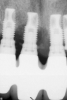

(1.) Peri-implantitis bone loss.

Figure 1

(2.) Peri-implantitis bone loss.

Figure 2

Peri-implantitis is defined as a bacterial plaque-associated pathological condition related to oral biofilm occurring in tissues around dental implants, characterized by inflammation in the peri-implant mucosa and subsequent progressive loss of surrounding bone1-8(Figure 1 and Figure 2). Food impaction is a contributing but not a primary factor in the disease process.